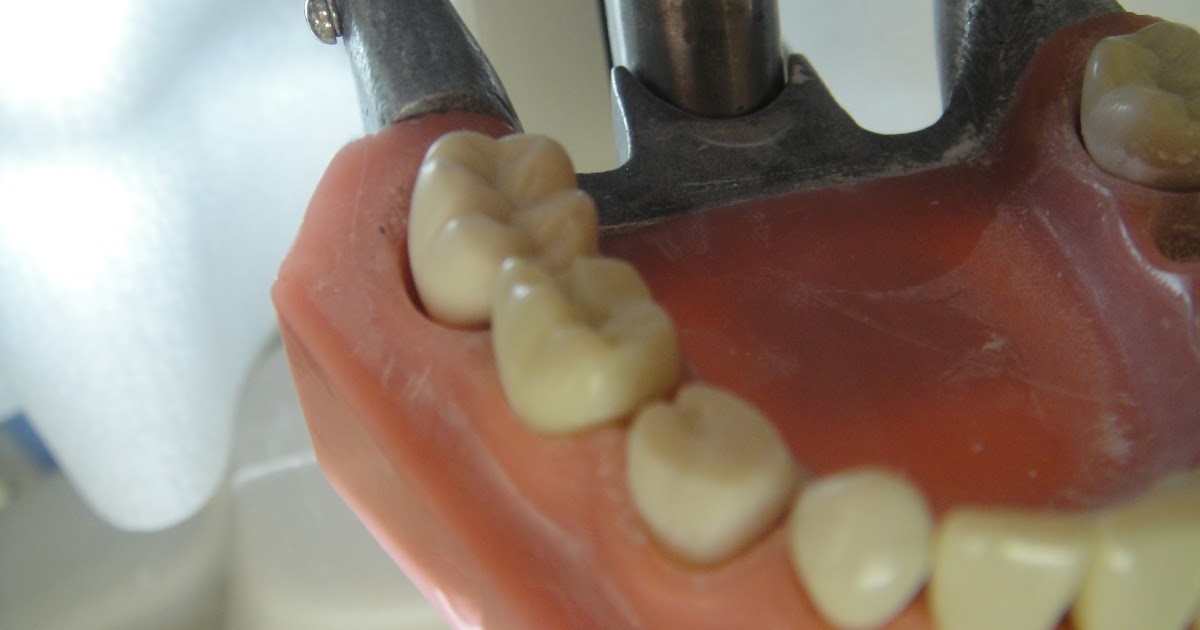

From www.stu-dentdiaries.com

StuDENT Diaries Pedo Stainless Steel Crown Stainless Steel Crown After Pulpotomy Stainless steel crowns are recommended as a permanent restoration after pulpotomy, while composite resin and amalgam. This split mouth, randomized controlled trial compared primary molars treated with white mta pulpotomies and restored with either multi. A stainless steel crown will be cemented onto the existing tooth, which becomes its new outer surface. Pulpotomies have been shown to have an 85%.. Stainless Steel Crown After Pulpotomy.

StuDENT Diaries Pedo Stainless Steel Crown Stainless Steel Crown After Pulpotomy This split mouth, randomized controlled trial compared primary molars treated with white mta pulpotomies and restored with either multi. Stainless steel crowns are recommended as a permanent restoration after pulpotomy, while composite resin and amalgam. A stainless steel crown will be cemented onto the existing tooth, which becomes its new outer surface. Pulpotomies have been shown to have an 85%.. Stainless Steel Crown After Pulpotomy.